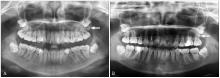

ST-TMR伴发病变 A:左下颌第三磨牙与ST-TMR呈对吻磨牙征伴囊性病变(箭头),37远中根吸收,38阻生;B:上颌双侧各1颗ST-TMR(黑箭头)伴2颗前牙区多生牙(白箭头),18、28阻生。"

图5

新增右上颌ST-TMR A:未见ST-TMR;B:2年后发现右上颌ST-TMR(箭头)。"